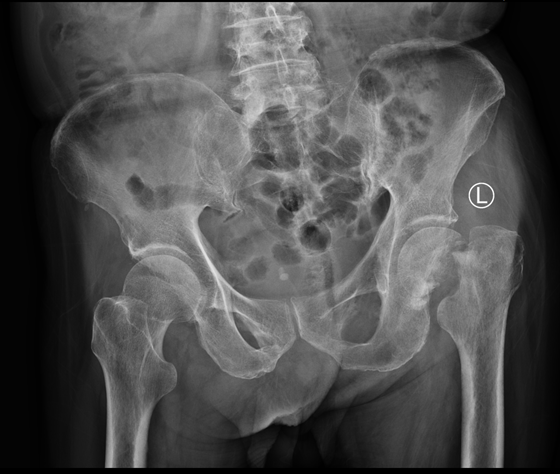

术前

2020年初,90岁高龄老人李爷爷在家活动时不慎摔倒,致左髋部疼痛、活动受限,站不起来了。家人顾及老人年龄,担心其安危,对于就医手术均持反对意见。老人的疼痛日渐加剧,家人于心不忍,准备将其送往医院时,恰逢新冠肺炎疫情暴发。家中的全家老小齐上阵照顾卧床老人,2个月时间,老人未出现任何压疮、血栓等并发症。待疫情平稳,家人赶紧将老人送到湘雅常德医院骨科。